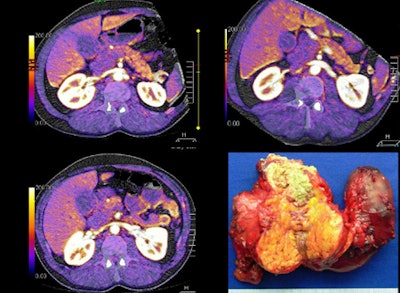

![]()  |

| Small 2-cm mass in the body of the pancreas, clearly imaged on the perfusion map. |